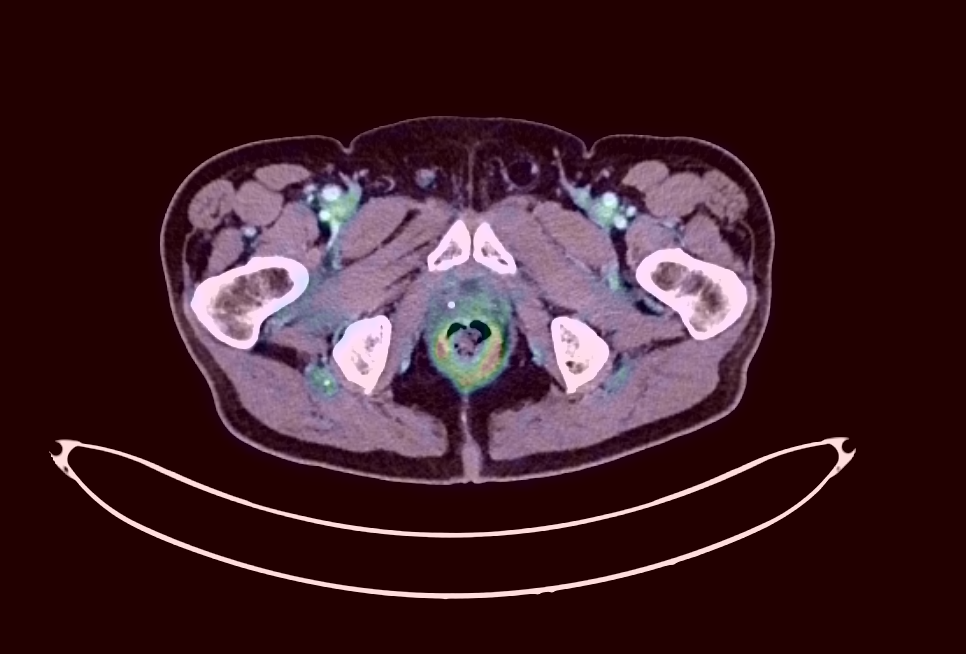

PET/CT Viewer

Native PET/CT viewing with true fusion display, SUV measurement, and Maximum Intensity Projection (MIP). Standard PACS systems often struggle to display PET scans natively — rendering them as static screenshots rather than interactive volumes, with no ability to measure SUV uptake, adjust colormap thresholds, or scroll through fused PET/CT slices.

Acurix renders PET and CT volumes as fully interactive overlays with adjustable fusion opacity, multiple PET colormaps, and real-time SUV quantification at any point in the volume. MIP projections provide a whole-body overview for rapid lesion localization — all from a standard web browser with no specialized workstation required.

PET/CT fusion viewer with SUV measurement, colormap overlay, and MIP projection